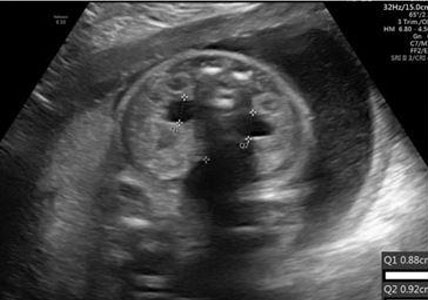

Imaging

On ultrasound, kidney size will be large for gestational age. Kidneys can become 3–10 times the normal size but may not enlarge until mid-second trimester [35] . A key diagnostic feature is diffusely echogenic kidneys. Notably, ultrasound findings will show a normal hypoechoic cortex and thin hypoechoic rim around echogenic medulla (Figure 13) [11]. This feature may be difficult to visualize in severe disease. Autosomal recessive polycystic kidney disease may also present with oligohydramnios, where the fetal bladder may not be visible. Indication of oligohydramnios is concerning for grim prognosis. Pulmonary hypoplasia, in which the chest is smaller in relation to the abdomen, may also be seen and be indicative of poor prognosis. On ultrasound, small discrete cysts may be visible, but do not predominate [11]. An MRI study will help with ambiguous ultrasound findings and will present similar, notable features.

Diagnostic checklist

If parents are known carriers, it is recommended to obtain several measurements of kidneys in the fetus. It is recommended to monitor amniotic fluid for oligohydramnios and measure thoracic circumference for pulmonary hypoplasia (Figure 13).

Figure 13: Ultrasound image showing enlarged hyperechogenic kidneys without cortico-medullary differentiation [26]. Radiological images were obtained from open-access article distributed under the terms of the Creative Commons Attribution License (CC BY) [26].